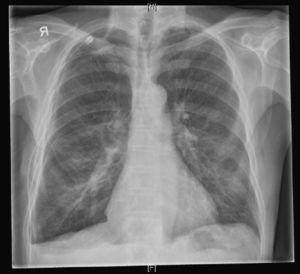

Pre-operative CXR (Fig. 2) showed a small right hydropneumothorax and a chest drain in place. No chest CT-scan was performed.